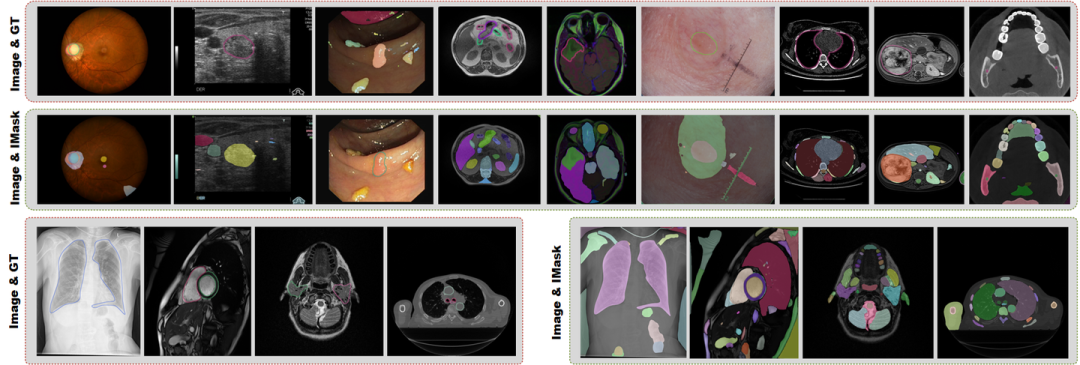

图2. IMed-361M数据集基本信息

03 统计与分析

IMed-361M数据集是迄今为止最大、公开可用的多模态交互式医学图像分割数据集,包含640万张图像、8760万个ground truth和2.734亿个交互式掩码,平均每张图像56个掩码。该数据集覆盖14种成像模态和204个分割目标,包括各主要器官及病变,涉及人体几乎所有部位。图像分辨率主要集中在256×256到1024×1024之间,确保研究场景的广泛适应性,大多数掩模占用的图像面积不足2%,反映了医学分割的细粒度特性。手动去除不相关的标注并应用过滤策略,仅保留有效掩模,从而增强模型在不同场景中的适应能力。